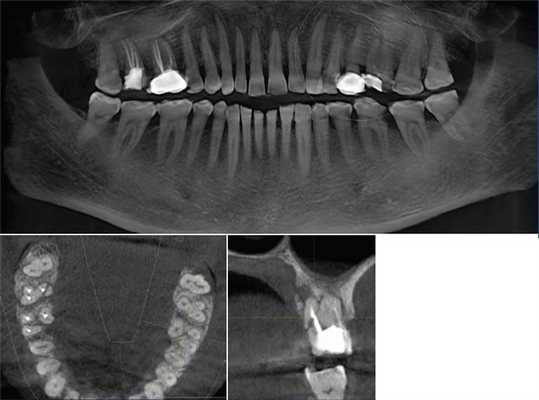

Выявлено, что у зубов с необтурированными КК при использовании распространенной в эндодонтической практике внутриротовой периапикальной рентгенографии, как правило, невозможно отчетливо визуализировать в каждом корне более 1 КК. В большинстве случаев это происходит из-за суммирования теней КК в каждом корне зуба (рис. 1, а; 2, а). В зоне нижней трети корней зубов отображение КК становилось нечетким либо вообще отсутствовало. При рентгенографии параллельной техникой изображение корней зубов было более качественным, чем при периапикальной съемке, но имело аналогичные закономерности (см. рис. 1, б). Использование для раздельной визуализации КК периапикальной рентгенографии в косой проекции приводило к ухудшению изображения нижних отделов корней всех групп зубов. На ОПМН КК зубов визуализировались недостаточно отчетливо (см. рис. 1, в).

Рис. 1. Исследование первого моляра верхней челюсти в эксперименте. При внутриротовой периапикальной рентгенографии (а), рентгенографии, выполненной параллельной техникой (б), в мезиальном щечном корне виден 1 КК; на фрагменте ОПМГ КК различаются нечетко (в); при КЛКТ на аксиальных срезах выявляются в мезиальном щечном корне 2 КК (г) и апикальные отверстия в дистальном щечном корне (д), на косом срезе определяется расположение корневых каналов (е).

Рис. 2. Исследование зуба 3.6. На внутриротовой периапикальной рентгенограмме (а) создается картина наличия только 1 канала в каждом из корней зуба; по данным аксиального среза КТ (б) отчетливо визуализируются по 2 КК в каждом из корней.

Рентгеновская КТ с построением аксиальных и косых срезов (см. рис. 1, г, д, е; 2, б) в сравнении с внутриротовой рентгенографией предоставляла объективные сведения о строении корней всех групп зубов. Информация о строении корней зубов, полученная при КТ перед эндодонтическими манипуляциями, позволяла заранее спланировать рациональную тактику лечения. В процессе эндодонтического лечения данные КТ способствовали сокращению времени на выявление устьев КК и повышению качества эндодонтического лечения.